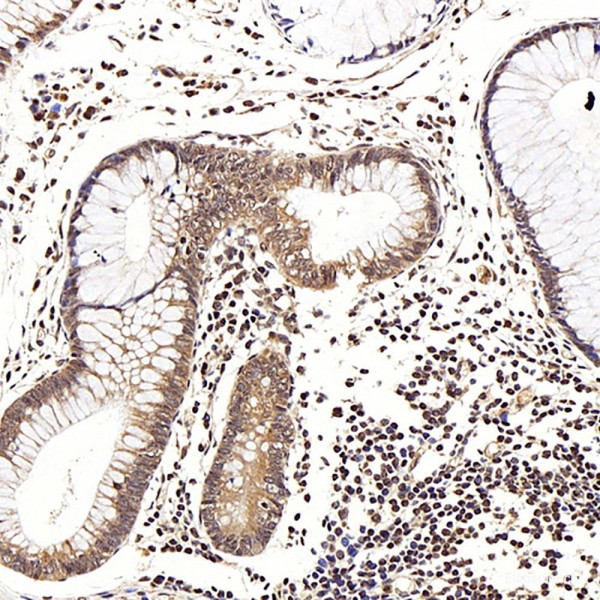

Product information "Anti-LEP"

| Application: | IHC |